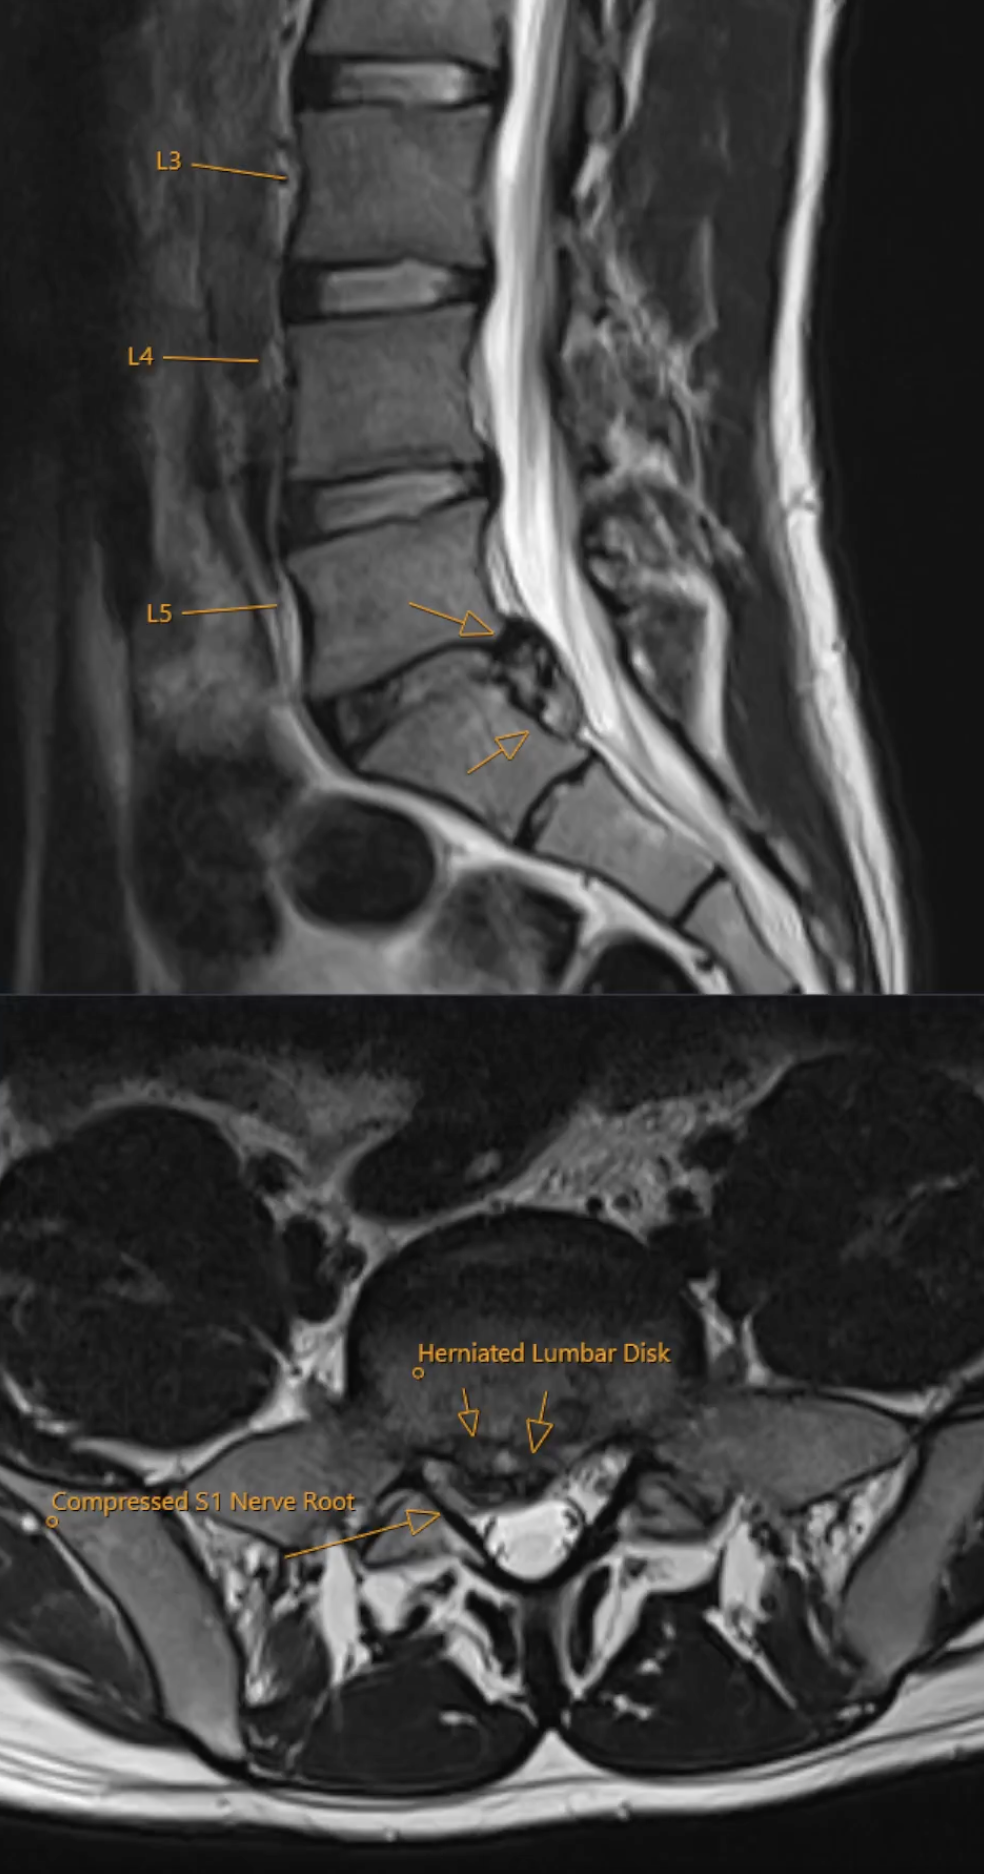

Herniated Lumbar Disk MRI

T2 sequences showing right sided paramedian disk herniation at L5-S1 level compressing right nerve root S1 in the lateral recess. No spinal stenosis.